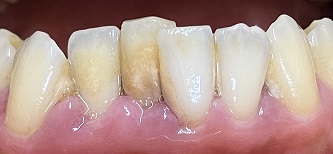

歯石は下の歯の裏側の歯の根元につきやすいのですが、口呼吸があるとそれに加えて唇側の歯の根本にもつきやすくなります。

口呼吸をすると、乾いた空気が直接、前歯の表面に当たり歯石がつきやすくなるからです。歯石は歯ブラシでとることはできないので

歯科医院での治療が必要になります。

唇側に歯石の付着 歯肉の腫れあり